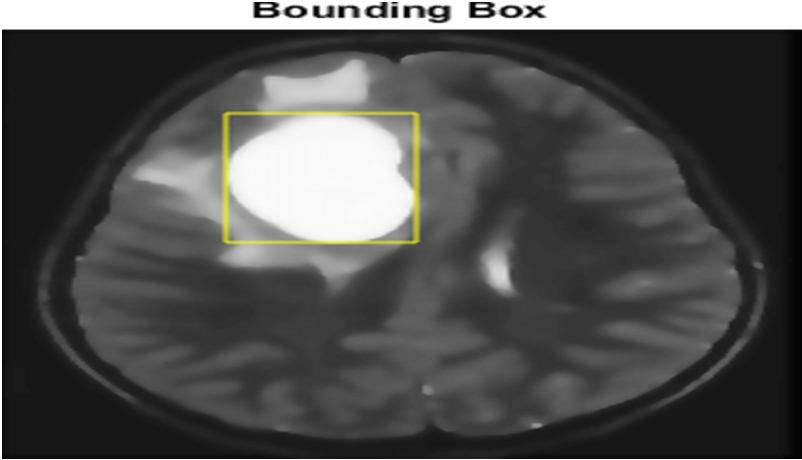

G. Bounding box

[4]The bounding box of an element is the smallest possible rectangle (aligned with the axes of that element's user coordinate system) that entirely encloses it and it is descendants. [5]When used in medical imaging, the bounding box refers to the border coordinates that enclose an image. They are often used to or identify bind a target and serve as a reference point for object detection and create a collision box for that object.

on MRI images

Fig 5 (a) Original image (b) Histogram graph of Fig. 4 (a) (c) Histogram of original images (d) histogram image of fig 4(c) Fig 8 bounding box applied